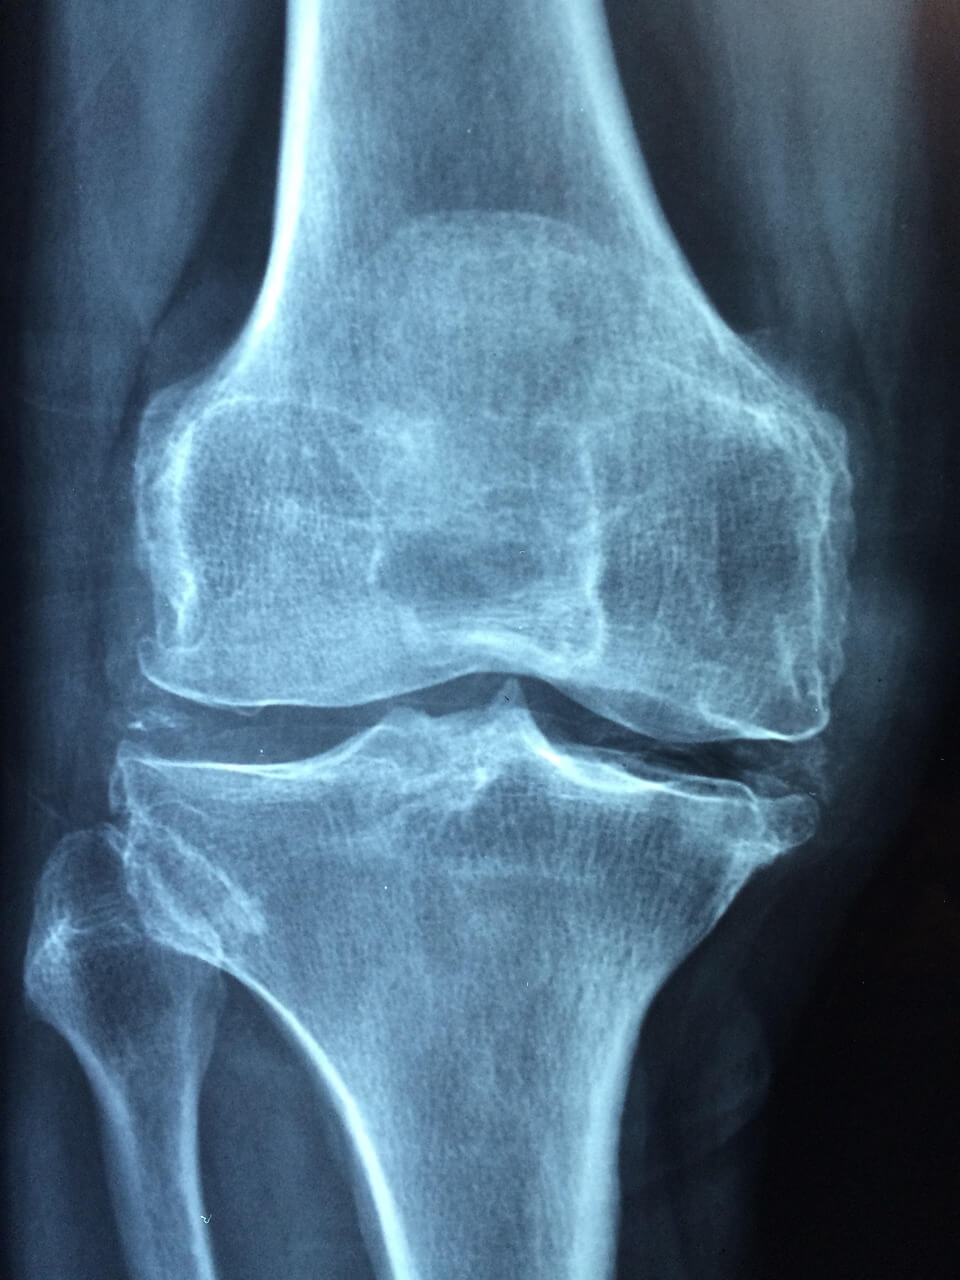

1. 전방십자인대란 무엇인가?

- 전방십자인대의 역할

전방십자인대는 무릎 안쪽 깊숙이 위치하며 대퇴골과 경골을 연결해 무릎이 앞뒤로 흔들리지 않도록 잡아주는 역할을 합니다. 쉽게 말해, 무릎의 중심을 지탱하는 ‘핵심 줄’과도 같습니다. 전방십자인대 파열이 일어나면 무릎이 헐거워지고, 체중을 지탱하기 어려워집니다.